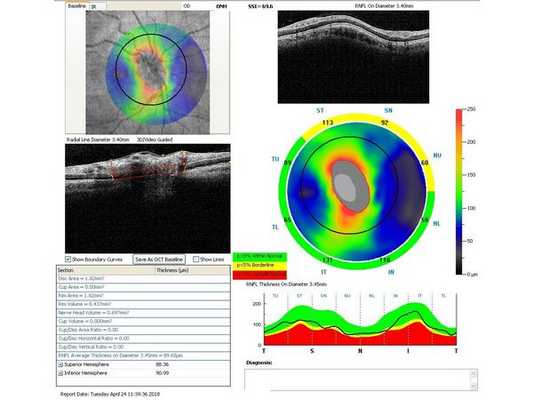

Гониоскопия выявила, что угол передней камеры глаза открыт, профиль радужки плоский, в углу передней камеры по всей окружности визуализируется резидуальная ткань, похожая на пигментированные отростки корня радужки. Она доходит до трабекулярной зоны. Также при первичном осмотре была проведена оптическая когерентная томография (ОКТ)(рис. 1-4).

Через неделю и через месяц после операции пациентка приходила на осмотры для проверки внутриглазного давления, остроты зрения и проведения ОКТ (рис. 5-8). Результаты обследований через месяц после лазерного лечения: ⠀•⠀Острота зрения: ⠀⠀⠀OD: 0,1 sph -2,0 cyl -0,75 ax 85 = 1,0; ⠀⠀⠀OS: 0,1 sph -2,5 cyl -0,75 ax 95 = 1,0. ⠀•⠀Поля зрений - без изменений. ⠀•⠀Тонометрия обоих глаз по Маклакову - 21 мм рт. ст. (без капель). ⠀•⠀Гониоскопическая картина без изменений.